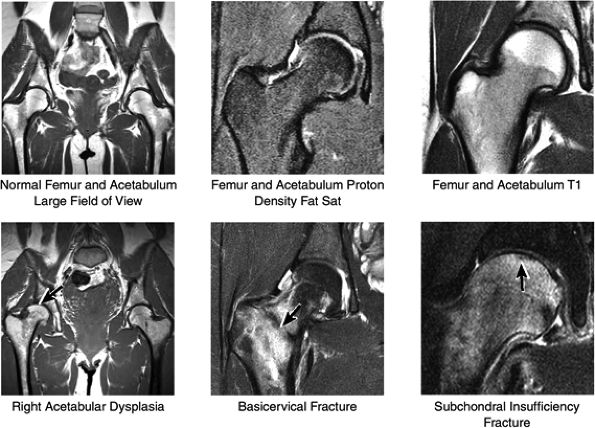

FIGURE 3.32 / Hip Cartilage.